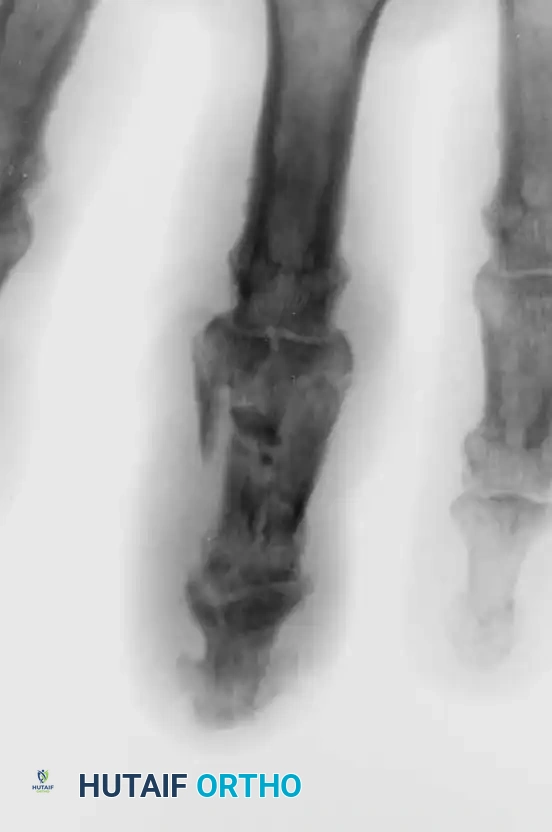

3. Comminuted Volar Fragment (≤40%): Volar Plate Arthroplasty

In PIP fracture-dislocations with a comminuted surface of the middle phalanx of 40% or less, or in persistent dorsal fracture-dislocations with preserved condyles of the proximal phalanx, the method of Eaton and Malerich (Volar Plate Arthroplasty) is indicated. This technique resurfaces the joint and restores the volar tether.

Open Reduction Technique (Eaton and Malerich):

* Make a volar incision using an elongated V with the flap based radially (or a standard Brunner zigzag incision).

* Excise the flexor tendon sheath (C1 and A3 pulleys) from the proximal phalanx sufficiently to allow the flexor tendons to be retracted laterally, exposing the entire volar aspect of the joint.

* Hyperextend the joint to identify the fracture in fresh injuries.

* The volar plate is usually still attached to the comminuted bone fragments of the middle phalanx. Detach the volar plate from these fragments.

* Excise the comminuted volar lip fragments to create a smooth transverse trough at the base of the middle phalanx.

* Advance the volar plate into this bony defect and secure it using a pull-out wire or suture anchors, effectively resurfacing the volar aspect of the joint and restoring stability.